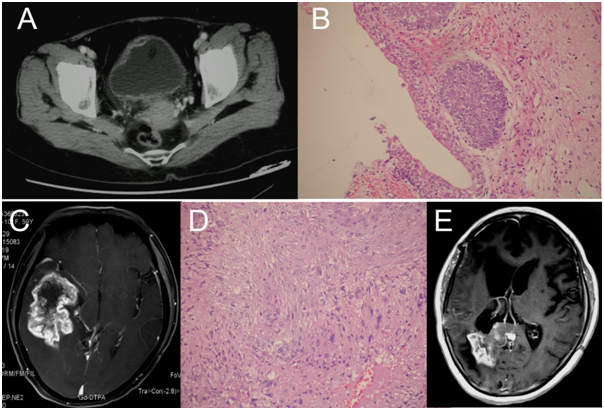

A 59-year-old female presented with a constant headache lasting for one week and was subsequently admitted. Two months before admission, she had suffered from invasive urothelial carcinoma, and a carcinectomy was performed to remove the bladder carcinoma (Figure 1A & 1B). In addition, no relatives of the patient had previously exhibited a similar disease. The physical examination of the patient revealed only slight disorientation, and no other obviously positive nervous system signs were observed at admission. A cranial MRI scans revealed right temporal lobe lesions suggesting the presence of a glioma or metastatic tumor (Figure 1C). We resected the tumor mass via surgery, and the post-operative pathological diagnosis was anaplastic astrocytoma (WHO grade Ⅲ, Figure 1D). The patient was then treated with combination chemotherapy (temozolomide and Nimustine) 6 times. An MRI rescan showed no obvious recurrence within 5 months of the operation, but a recurrence at the homolateral temporal horn appeared 7 months post-operation (Figure 1E). However, the patient refused further treatment and died 12 months after the glioma resection.

Figure 1 Radiological and pathological examinations. A) A pelvic cavity CT scan revealed an invasive lesion in the right anterior wall of the bladder (arrow); B) Post-operative pathological examination confirmed the diagnosis of high grade bladder cancer (200×); C) A cranial MRI scan showed a right temporal lobe lesion with uneven enhancement after injection of Gd-DTPA; D) The pathological diagnosis for the intracranial mass was anaplastic astrocytoma (200×); E, the MRI scan 7 months after glioma resection showed a recurrence in the right temporal horn.